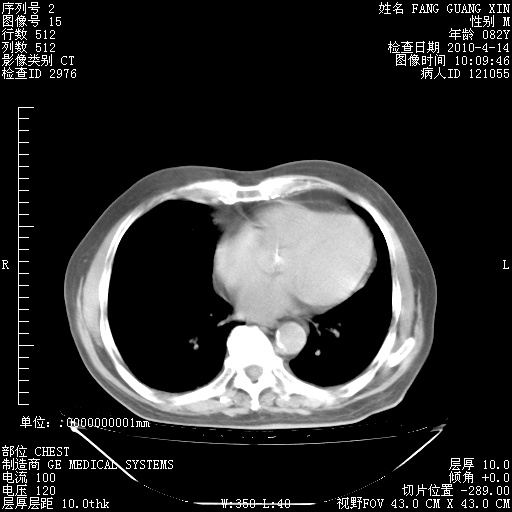

肺部CT平扫未见异常。